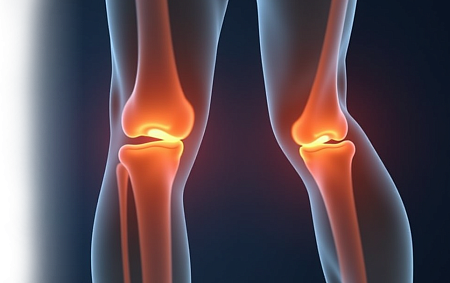

УЗИ коленного сустава

УЗИ коленного сустава – безопасный и неинвазивный метод исследования, который позволяет оценить состояние мягких тканей и структур в области колена.